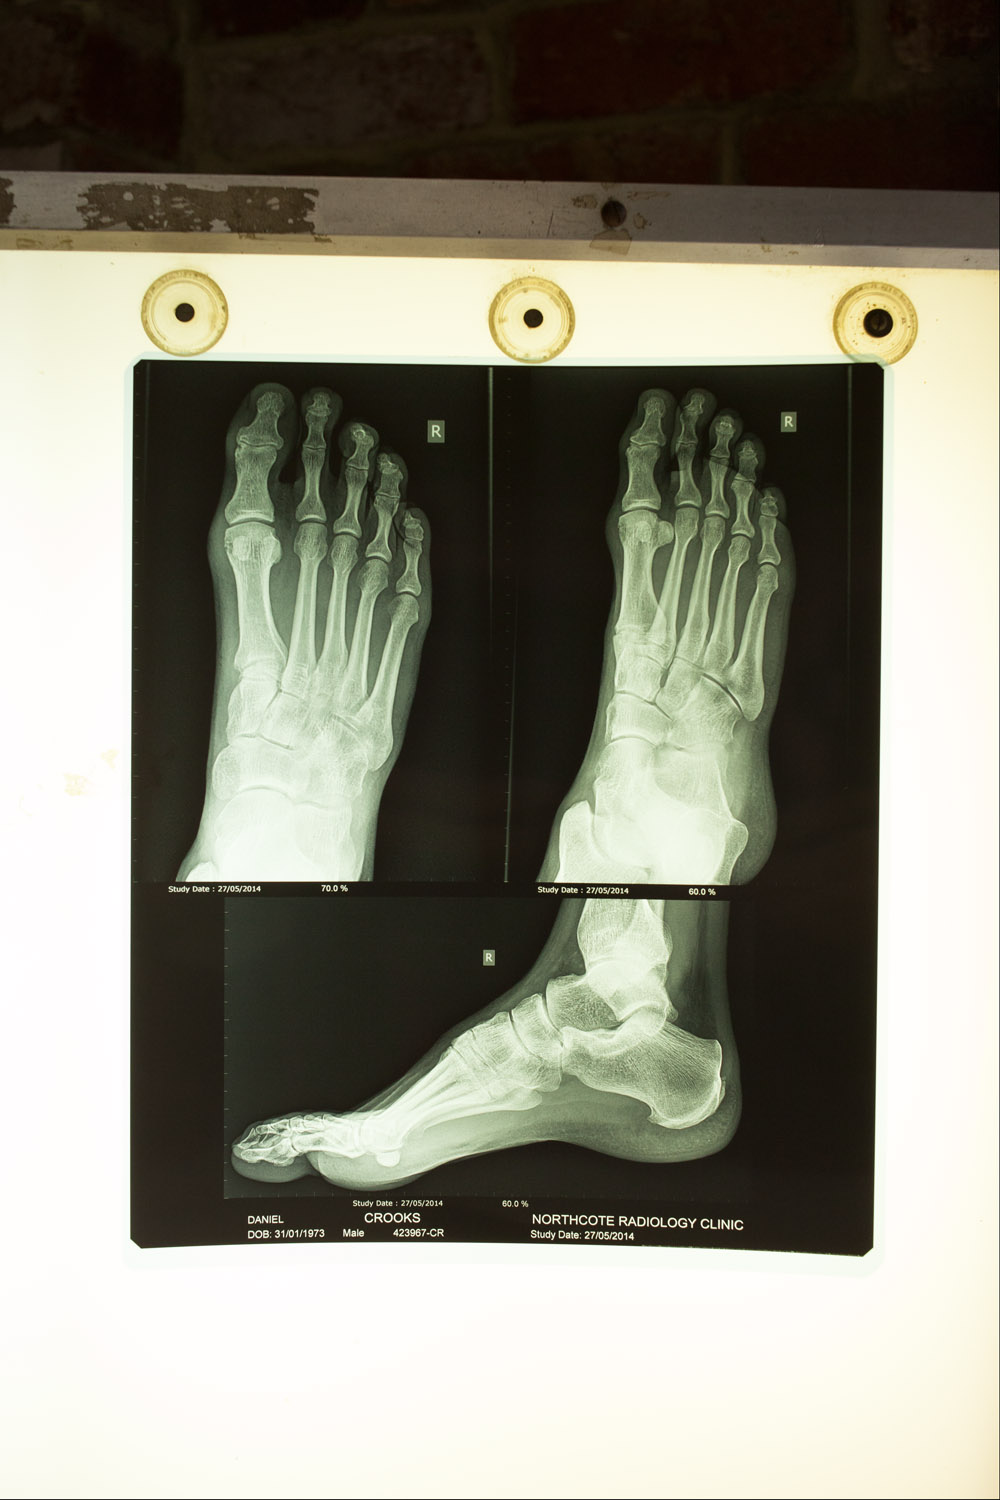

irrefutable evidence June 13, 2014injuryfucked, x-raystriker Almost a year later the foot is still sore, X-rays show “…early osteoarthritis involving the distal interphalangeal joint of the big toe and a fracture near the head of the proximal phalanx…”. Awesome.